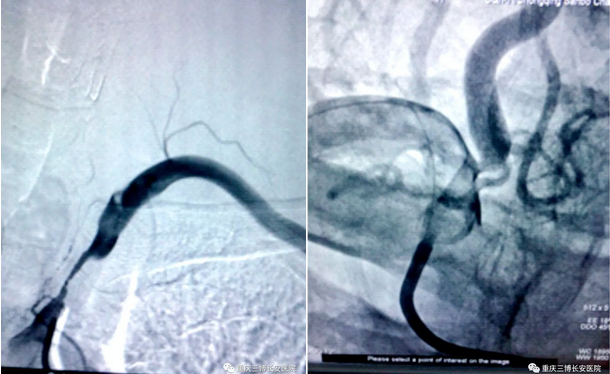

在重庆三博长安医院脑血管病中心,神经内科团队接诊了这位特殊病人,韩显文主任立即组织神经介入团队刘庆林主治医师、栾建芳主治医师、郑敬帮医师等做了详细的病例讨论,决定为刘先生做头颈部血管DSA造影检查。

在DSA造影检查中发现,刘先生为左手提供血液供应的左锁骨下动脉起始部严重狭窄,几乎闭塞,致左侧上肢血液无法供给。左锁骨下动脉有一个分支,叫左侧椎动脉,该动脉向大脑供血,也无法正常供血。同时还发现刘先生右侧椎动脉起始部也严重狭窄,右侧椎动脉血液从主动脉弓缓缓流向大脑,血液在即将进入大脑的时候,部分血液调了个头,转弯经左侧椎动脉反向流向左手,导致大脑供血严重不足。刘先生血液倒流的原因找到,脑梗反复发作,并且越来越重的原因找到。